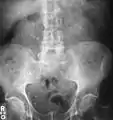

Imaging studies

Calcium-containing stones are relatively radiodense, and they can often be detected by a traditional radiograph of the abdomen that includes the kidneys, ureters, and bladder (KUB film).[58] KUB radiograph, although useful in monitoring size of stone or passage of stone in stone formers, might not be useful in the acute setting due to low sensitivity.[59] Some 60% of all renal stones are radiopaque.[60][61] In general, calcium phosphate stones have the greatest density, followed by calcium oxalate and magnesium ammonium phosphate stones. Cystine calculi are only faintly radiodense, while uric acid stones are usually entirely radiolucent.[62]

Bilateral kidney stones can be seen on this KUB radiograph. There are phleboliths in the pelvis, which can be misinterpreted as bladder stones.